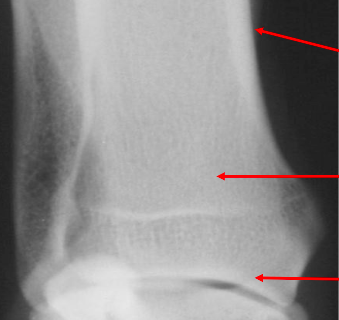

Q

what is the arrow pointing to?

A

an apophysis, a separate ossification center. this one is the tibial tuberosity